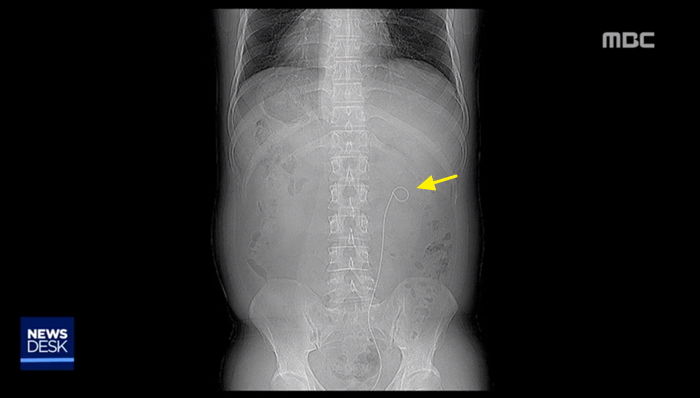

일상생활에 지장을 받을 정도가 되자 박씨는 지난 10월, 정확한 검진을 위해 병원에서 엑스레이 사진을 촬영했다.

결과는 매우 충격적이었다. 박씨의 뱃속에는 약 3년 9개월 전 받은 수술에서 사용했던 30cm 길이의 철사가 고스란히 남아있었다.